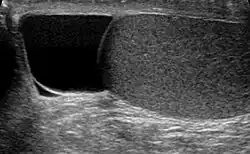

| Ultrasound of a testicle (grey) and a spermatocele (black). | |

The primary care physician may diagnose and manage benign causes of scrotal masses such as hydrocele, varicocele and spermatocele. However, if a "must not miss" diagnosis related to testicular masses such as testicular torsion, epididymitis, acute orchitis, strangulated hernia and testicular cancer is suspected, the family physician must refer to a urologist.[19] Finding a painless, cystic mass at the head of the epididymis that is clearly separate from the testicle can indicate a spermatocele. Shining a light through the mass, a process known as transillumination, can also help differentiate between a fluid-filled cyst and a tumor, which would not allow as much light to pass.[20] If uncertainty exists, ultrasonography of the scrotum can confirm the presence of a spermatocele.[7] The location and history of any scrotal masses are crucial in determining whether or not the mass is benign or malignant.[21] Lab tests such as a complete blood count (CBC test) or urine test can also be conducted to check for any possible infection or signs of inflammation.[22]

Although the evidence and information for incidence of spermatoceles in children is lacking, there are general management guidelines for caregivers who may encounter spermatoceles in their children.[9] Epididymal cysts are typically benign in nature. However, caregivers should take note of any discomfort and symptoms in children, including but not limited to, erythema, scrotal edema or swelling.[9] Epididymal cysts appear in approximately 70% of boys who present as asymptomatic.[9] The diagnosis of epididymal cysts in children can be discovered upon physical examination and eventually confirmed via ultrasound.[9]

Upon physical examination, if a 'lump' is found during the testicular exam, further screening may be performed via ultrasound to eliminate testicular cancer.[18]